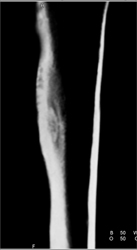

Osteoid Osteoma